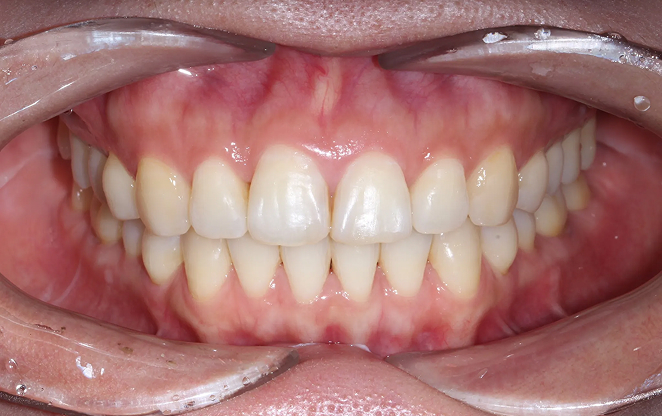

Before

After